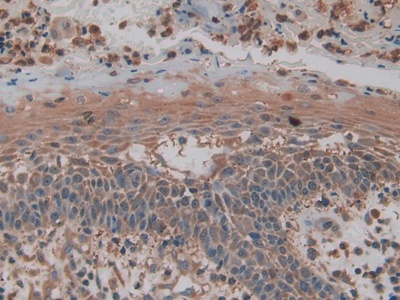

Использование высококачественных первичных антител является неотъемлемым условием получения точных и воспроизводимых результатов в современных научных исследованиях. Например, в рамках онкологического исследования удалось достоверно идентифицировать экспрессию белка PD-L1, что сыграло ключевую роль в оценке потенциальной эффективности иммунотерапии. Применение надежных антител обеспечило стабильность сигнала и высокую специфичность детекции, что позволило получить данные, пригодные для публикации в рецензируемых научных изданиях.